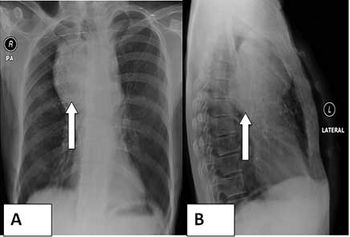

Case History: 58-year-old patient with dyspnoea for eight months. No history of fever. Lab exam and history were unremarkable.